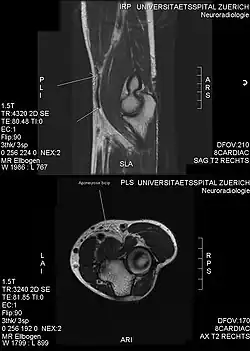

Another injury caused by bicep curls is ulnar neuropathy, which lead to ulnar nerve conduction slowing at the elbow. This is caused by compression of the nerves against a weight bench during the exercise.[22] Though unlikely, bicep curl can cause a rupture of the pectoralis major muscle, which is a severe injury that occurs in the chest.[23]